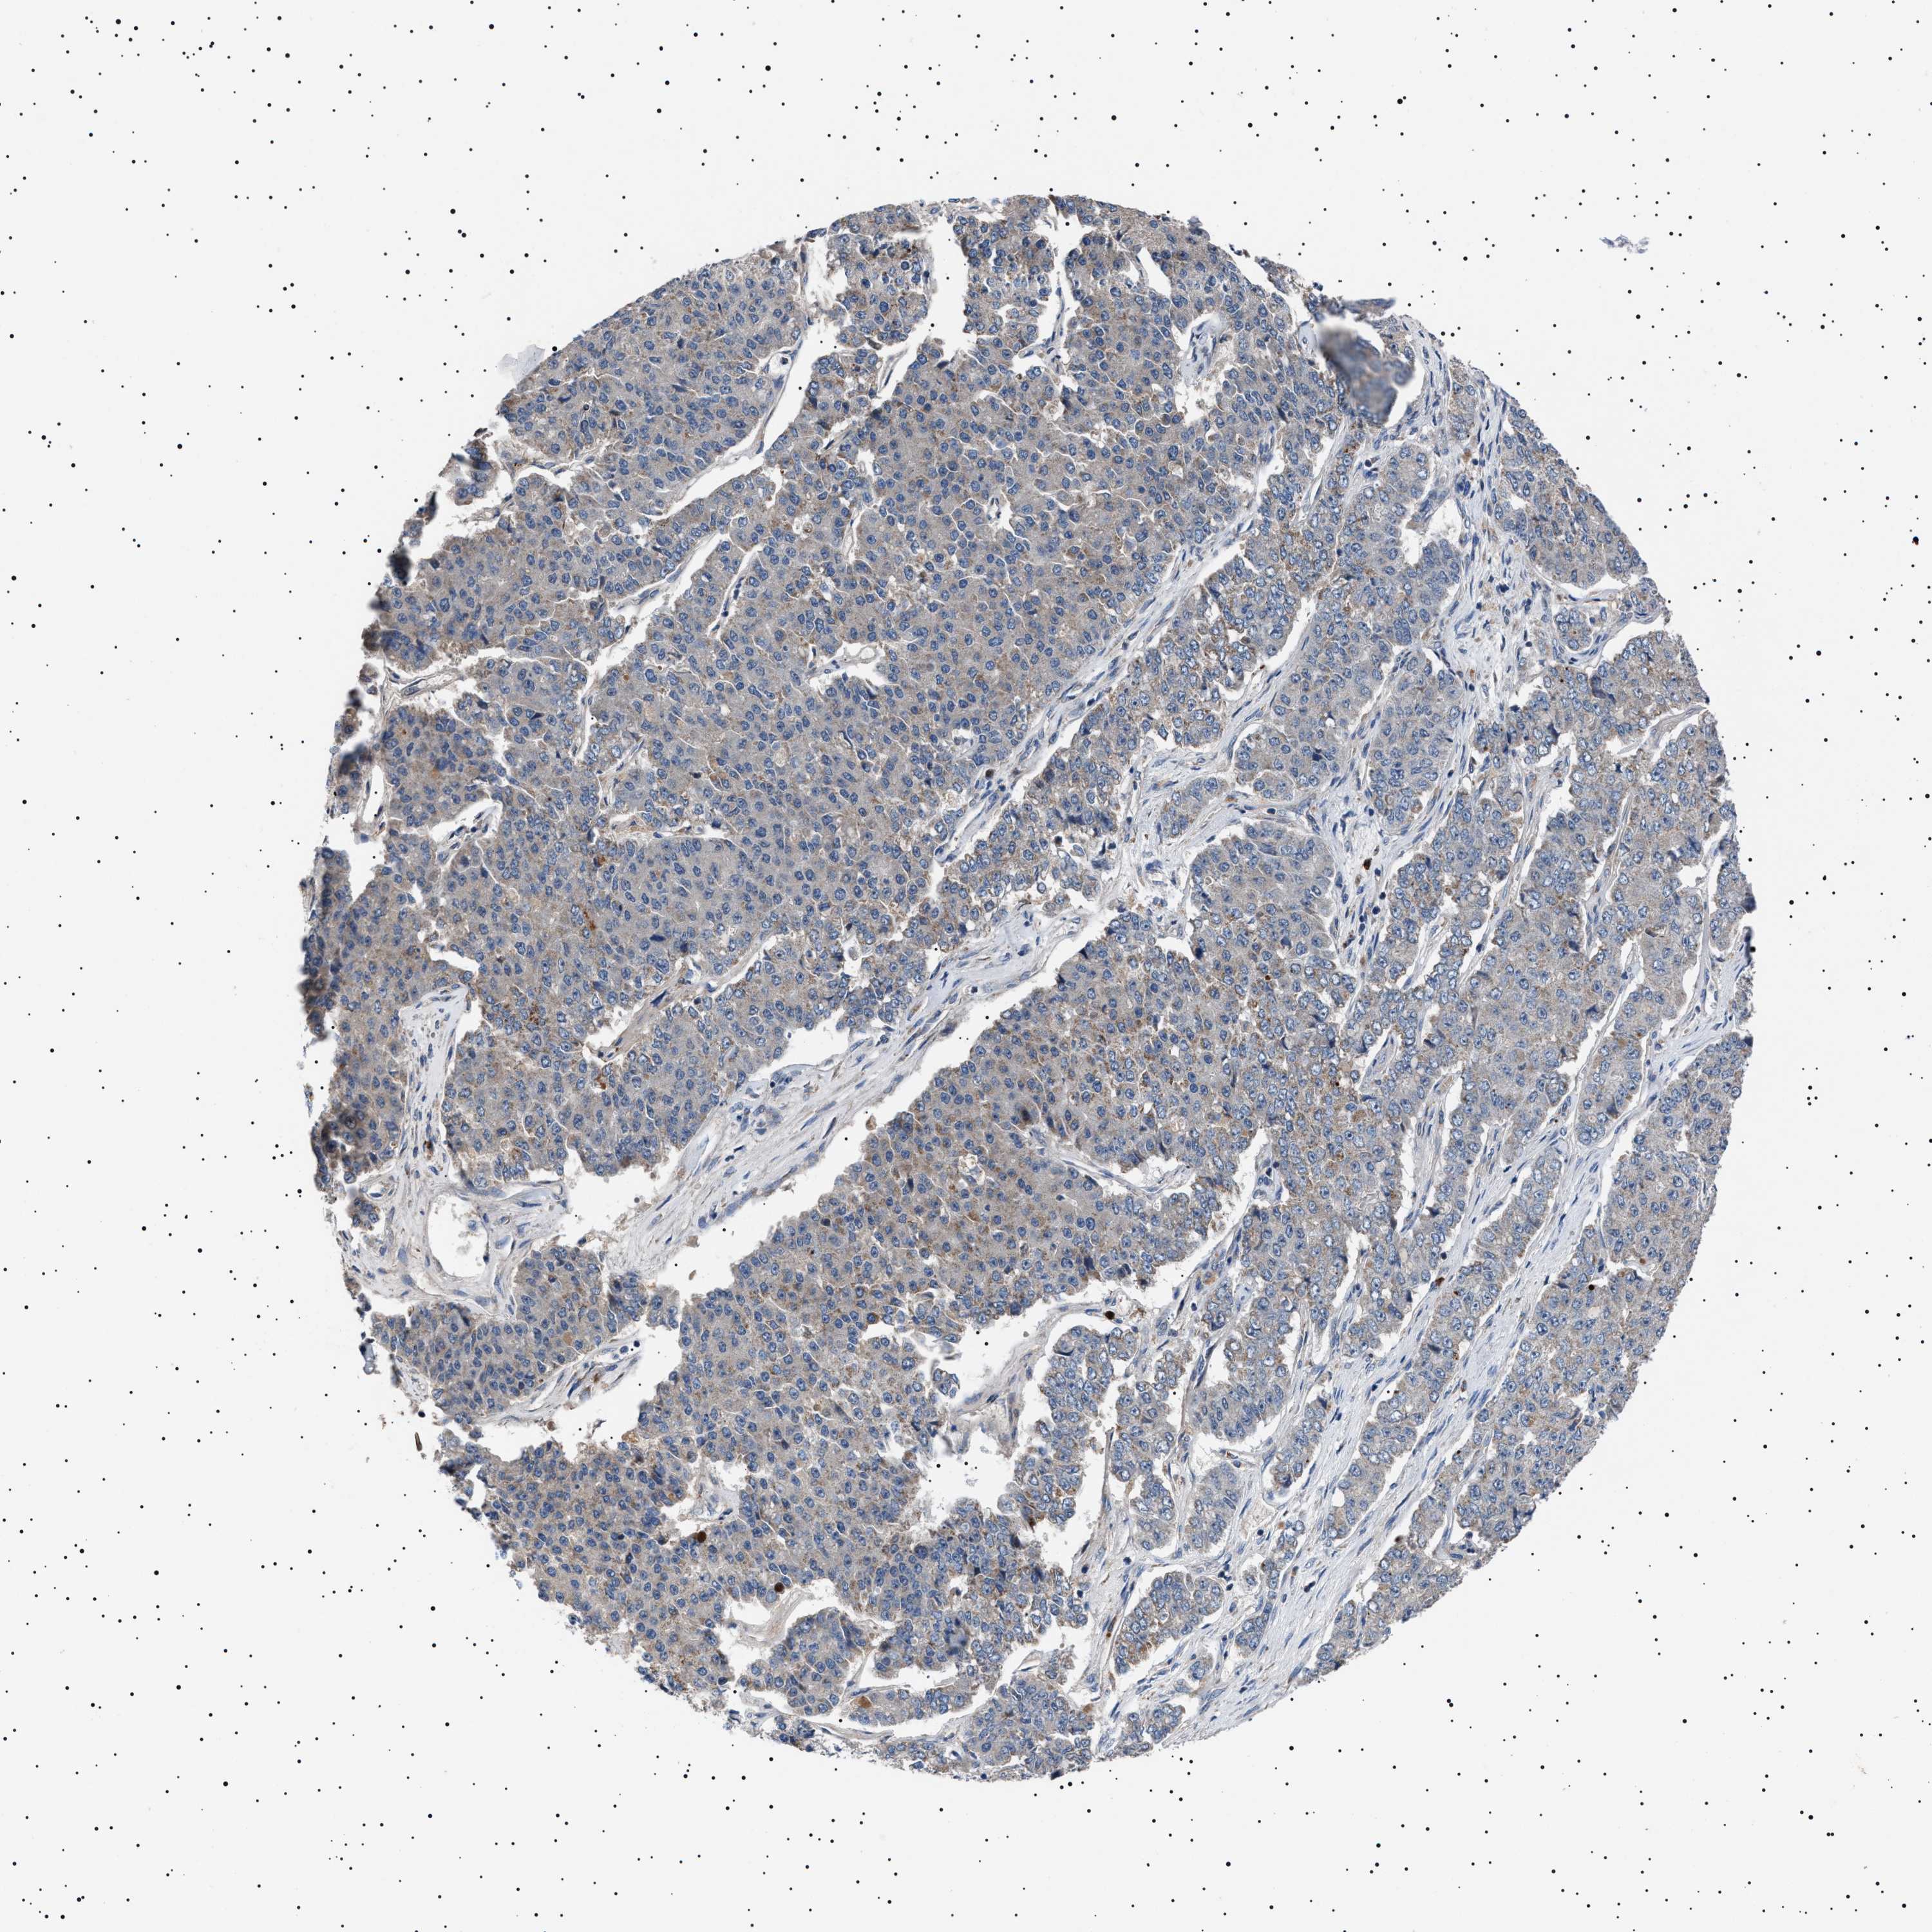

PANCREATIC CANCER - Protein expressioni

A mouse-over function shows sample information and annotation data. Click on an image to view it in a full screen mode. Samples can be filtered based on level of antibody staining by selecting one or several of the following categories: high, medium, low and not detected. The assay and annotation is described here.

Note that samples used for immunohistochemistry by the Human Protein Atlas do not correspond to samples in the TCGA dataset.

Antibody stainingi

Antibody staining in the annotated cell types in the current human tissue is reported as not detected, low, medium, or high, based on conventional immunohistochemistry profiling in selected tissues. This score is based on the combination of the staining intensity and fraction of stained cells.

Each image is clickable and will lead to virtual microscopy that enables deeper exploration of all samples and also displays staining intensity scores, fraction scores and subcellular localization as well as patient and tissue information for each sample.

Antibody HPA021223

Staining

High

Medium

Low

Not detected

Intensity

Strong

Moderate

Weak

Negative

Quantity

>75%

75%-25%

<25%

None

Location

Nuclear

Cytoplasmic/membranous

Cytoplasmic/membranous,nuclear

Adenocarcinoma, NOS